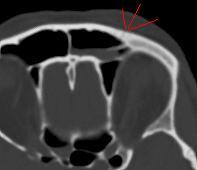

Результат МСКТ-костей черепа и головного мозга:

На станции вроде бы всё настроил, чёткость несколько сбилась изображений, вообще ссадина была слева и слева видно в ячейке лобной пазухи жидкость плотность крови(55HU), была сделана реконструкция с интервалом 1,5мм. Перелмо передней стенки ячейки лобной пазухи, можно даже так сказать "трещина" и гемосинус: